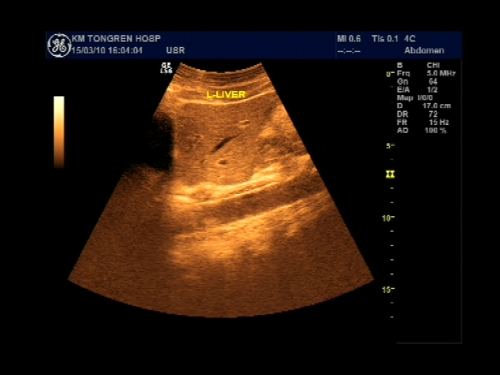

超声声像图能显示肝脏切面形态、大小、肝内实质结构、管道系统及肝周邻,并能根据肝内管道系统区分肝脏各叶、各段,对病变进行定位诊断。彩色多普勒超声能显示肝脏的血流,并能对肝脏的血流动力学参数进行测定,不仅能诊断肝脏的血管病变,还能了解正常肝脏及病变肝脏的血供及回流状态,目前已成为临床诊断肝脏疾病的常规检查方法。

纵断扫查

肝脏超声以肝内管道的一级、二级、三级分支未基础,将肝脏分为五叶8段:尾叶(Ⅰ)、左外叶上段(Ⅱ)、左外叶下段(Ⅲ)、左内叶(Ⅳ)、右前叶下段(Ⅴ)、右后叶下段(Ⅵ)、右后叶上段(Ⅶ)、右前叶上段(Ⅷ)